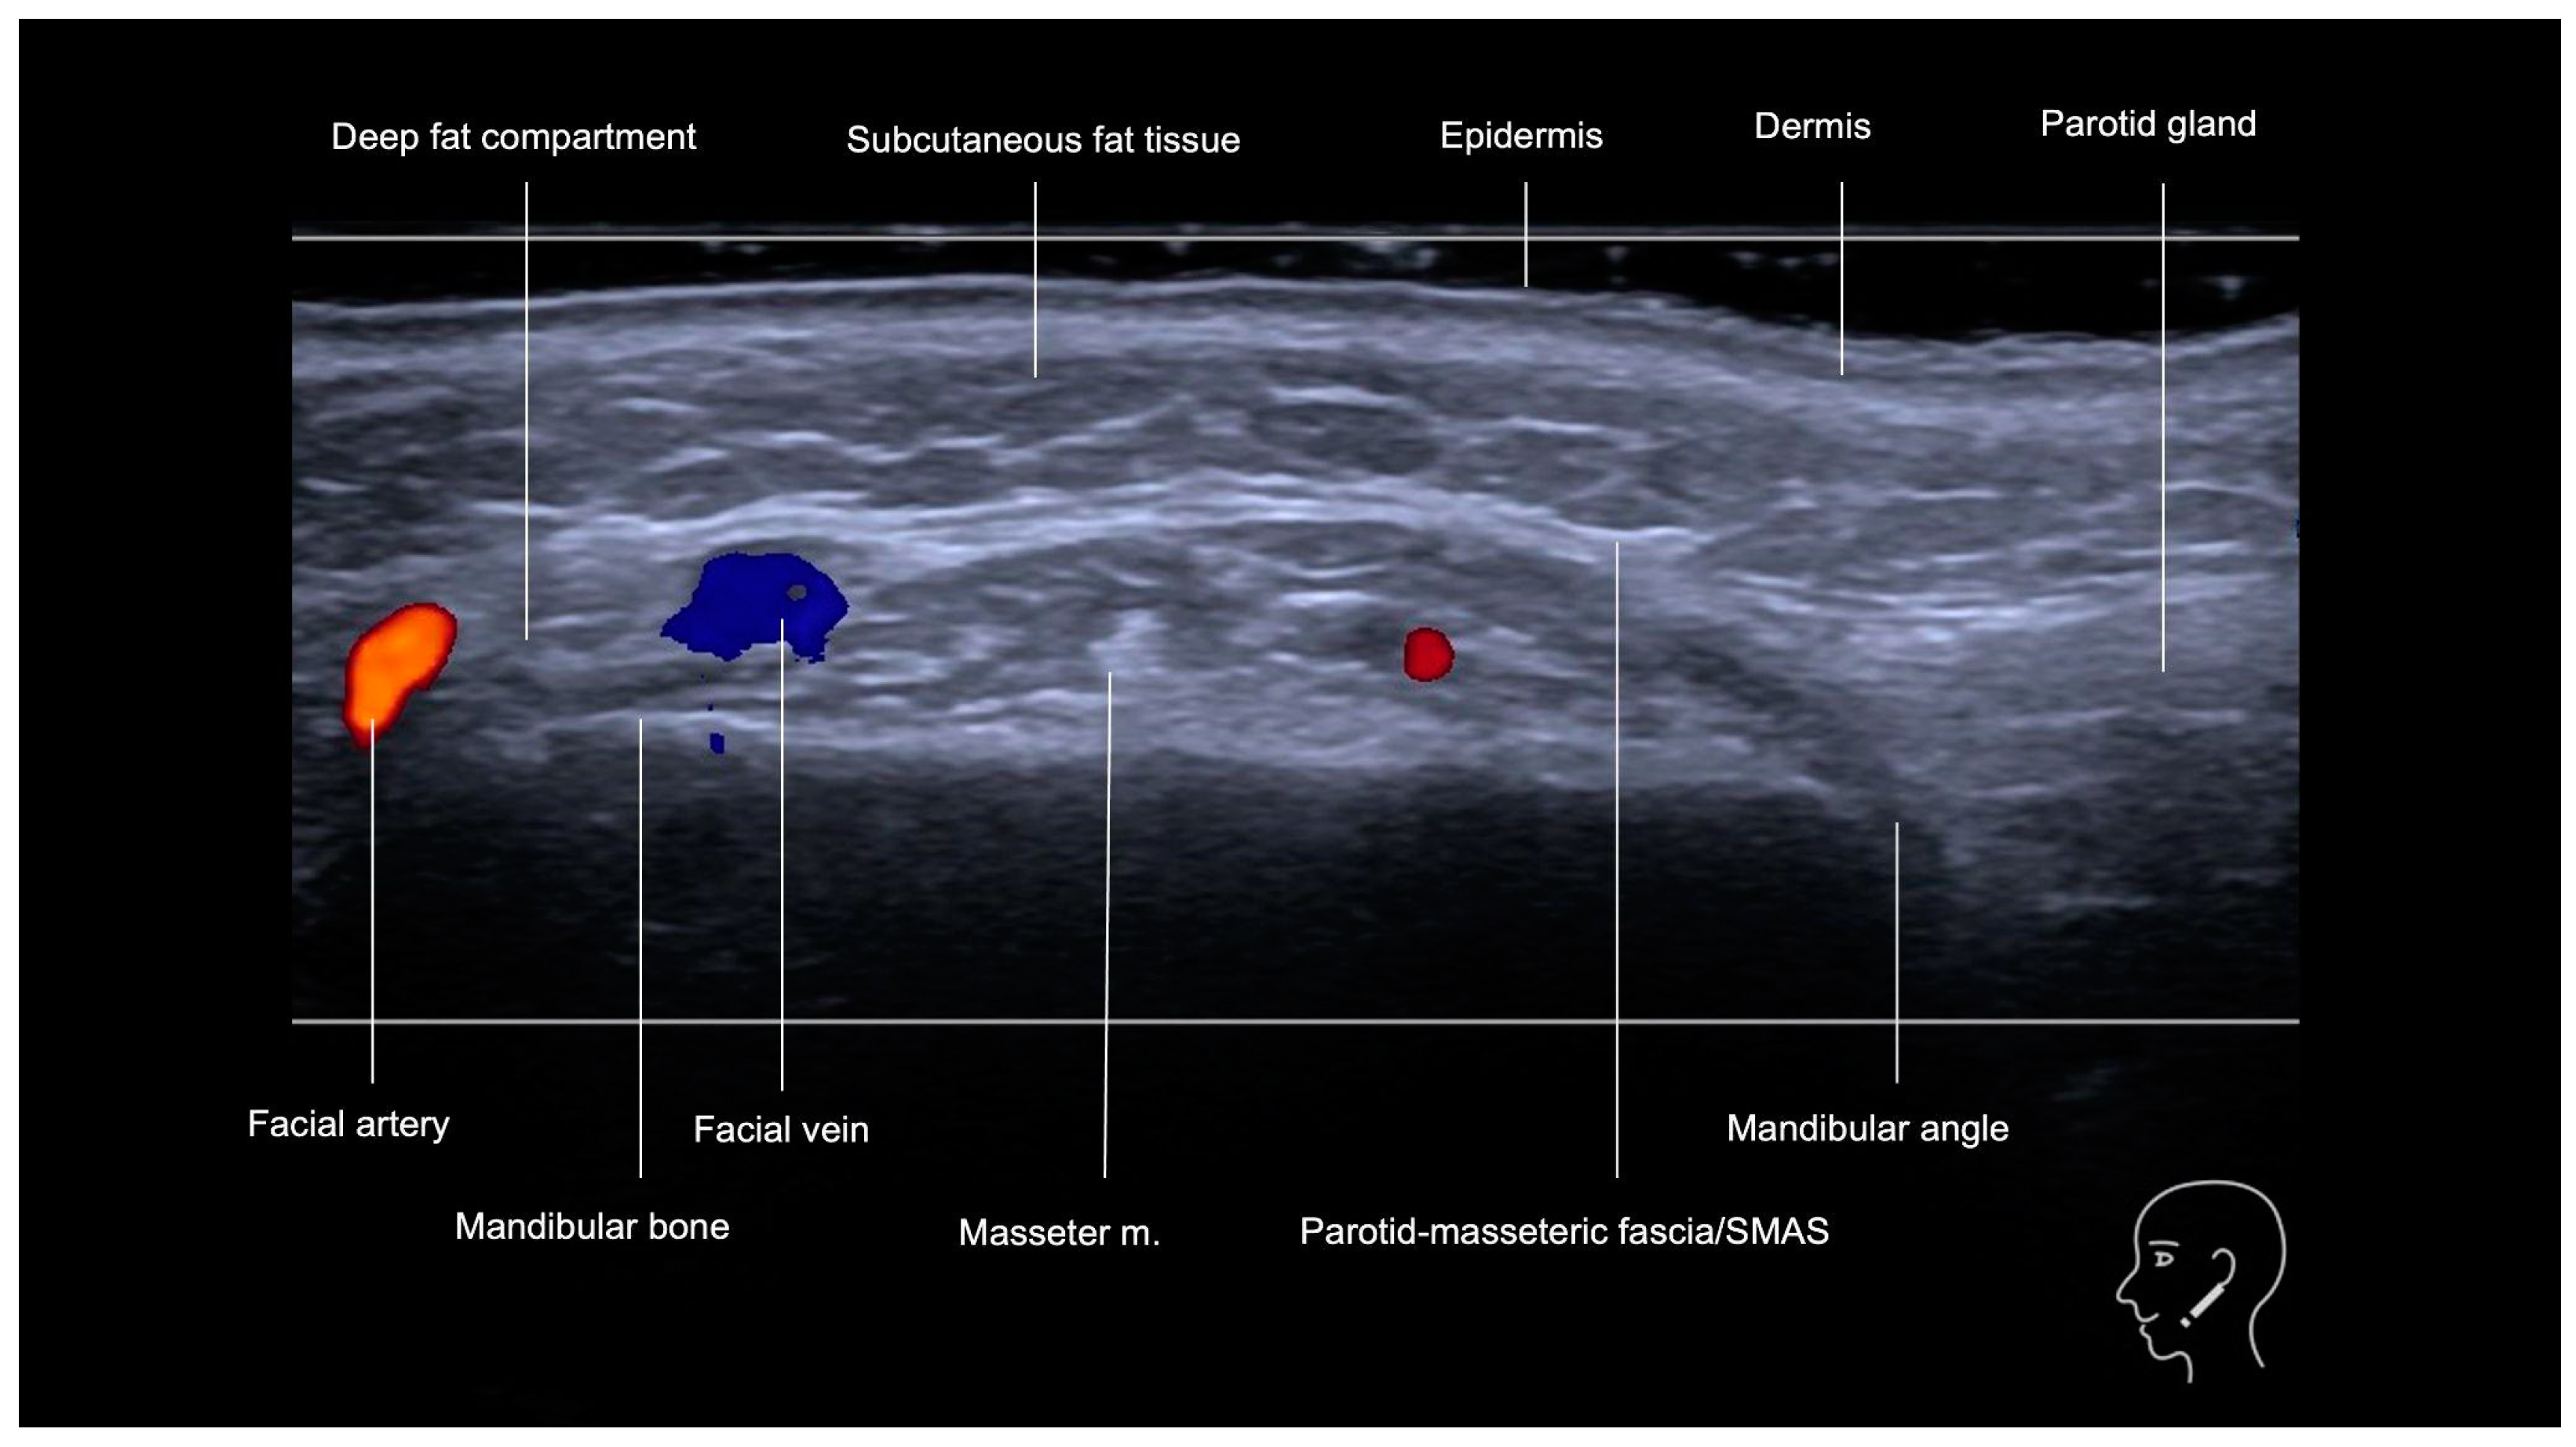

3.1. Mandibular Region (Posterior and Anterior)

3.1.1. Sonographic Anatomy